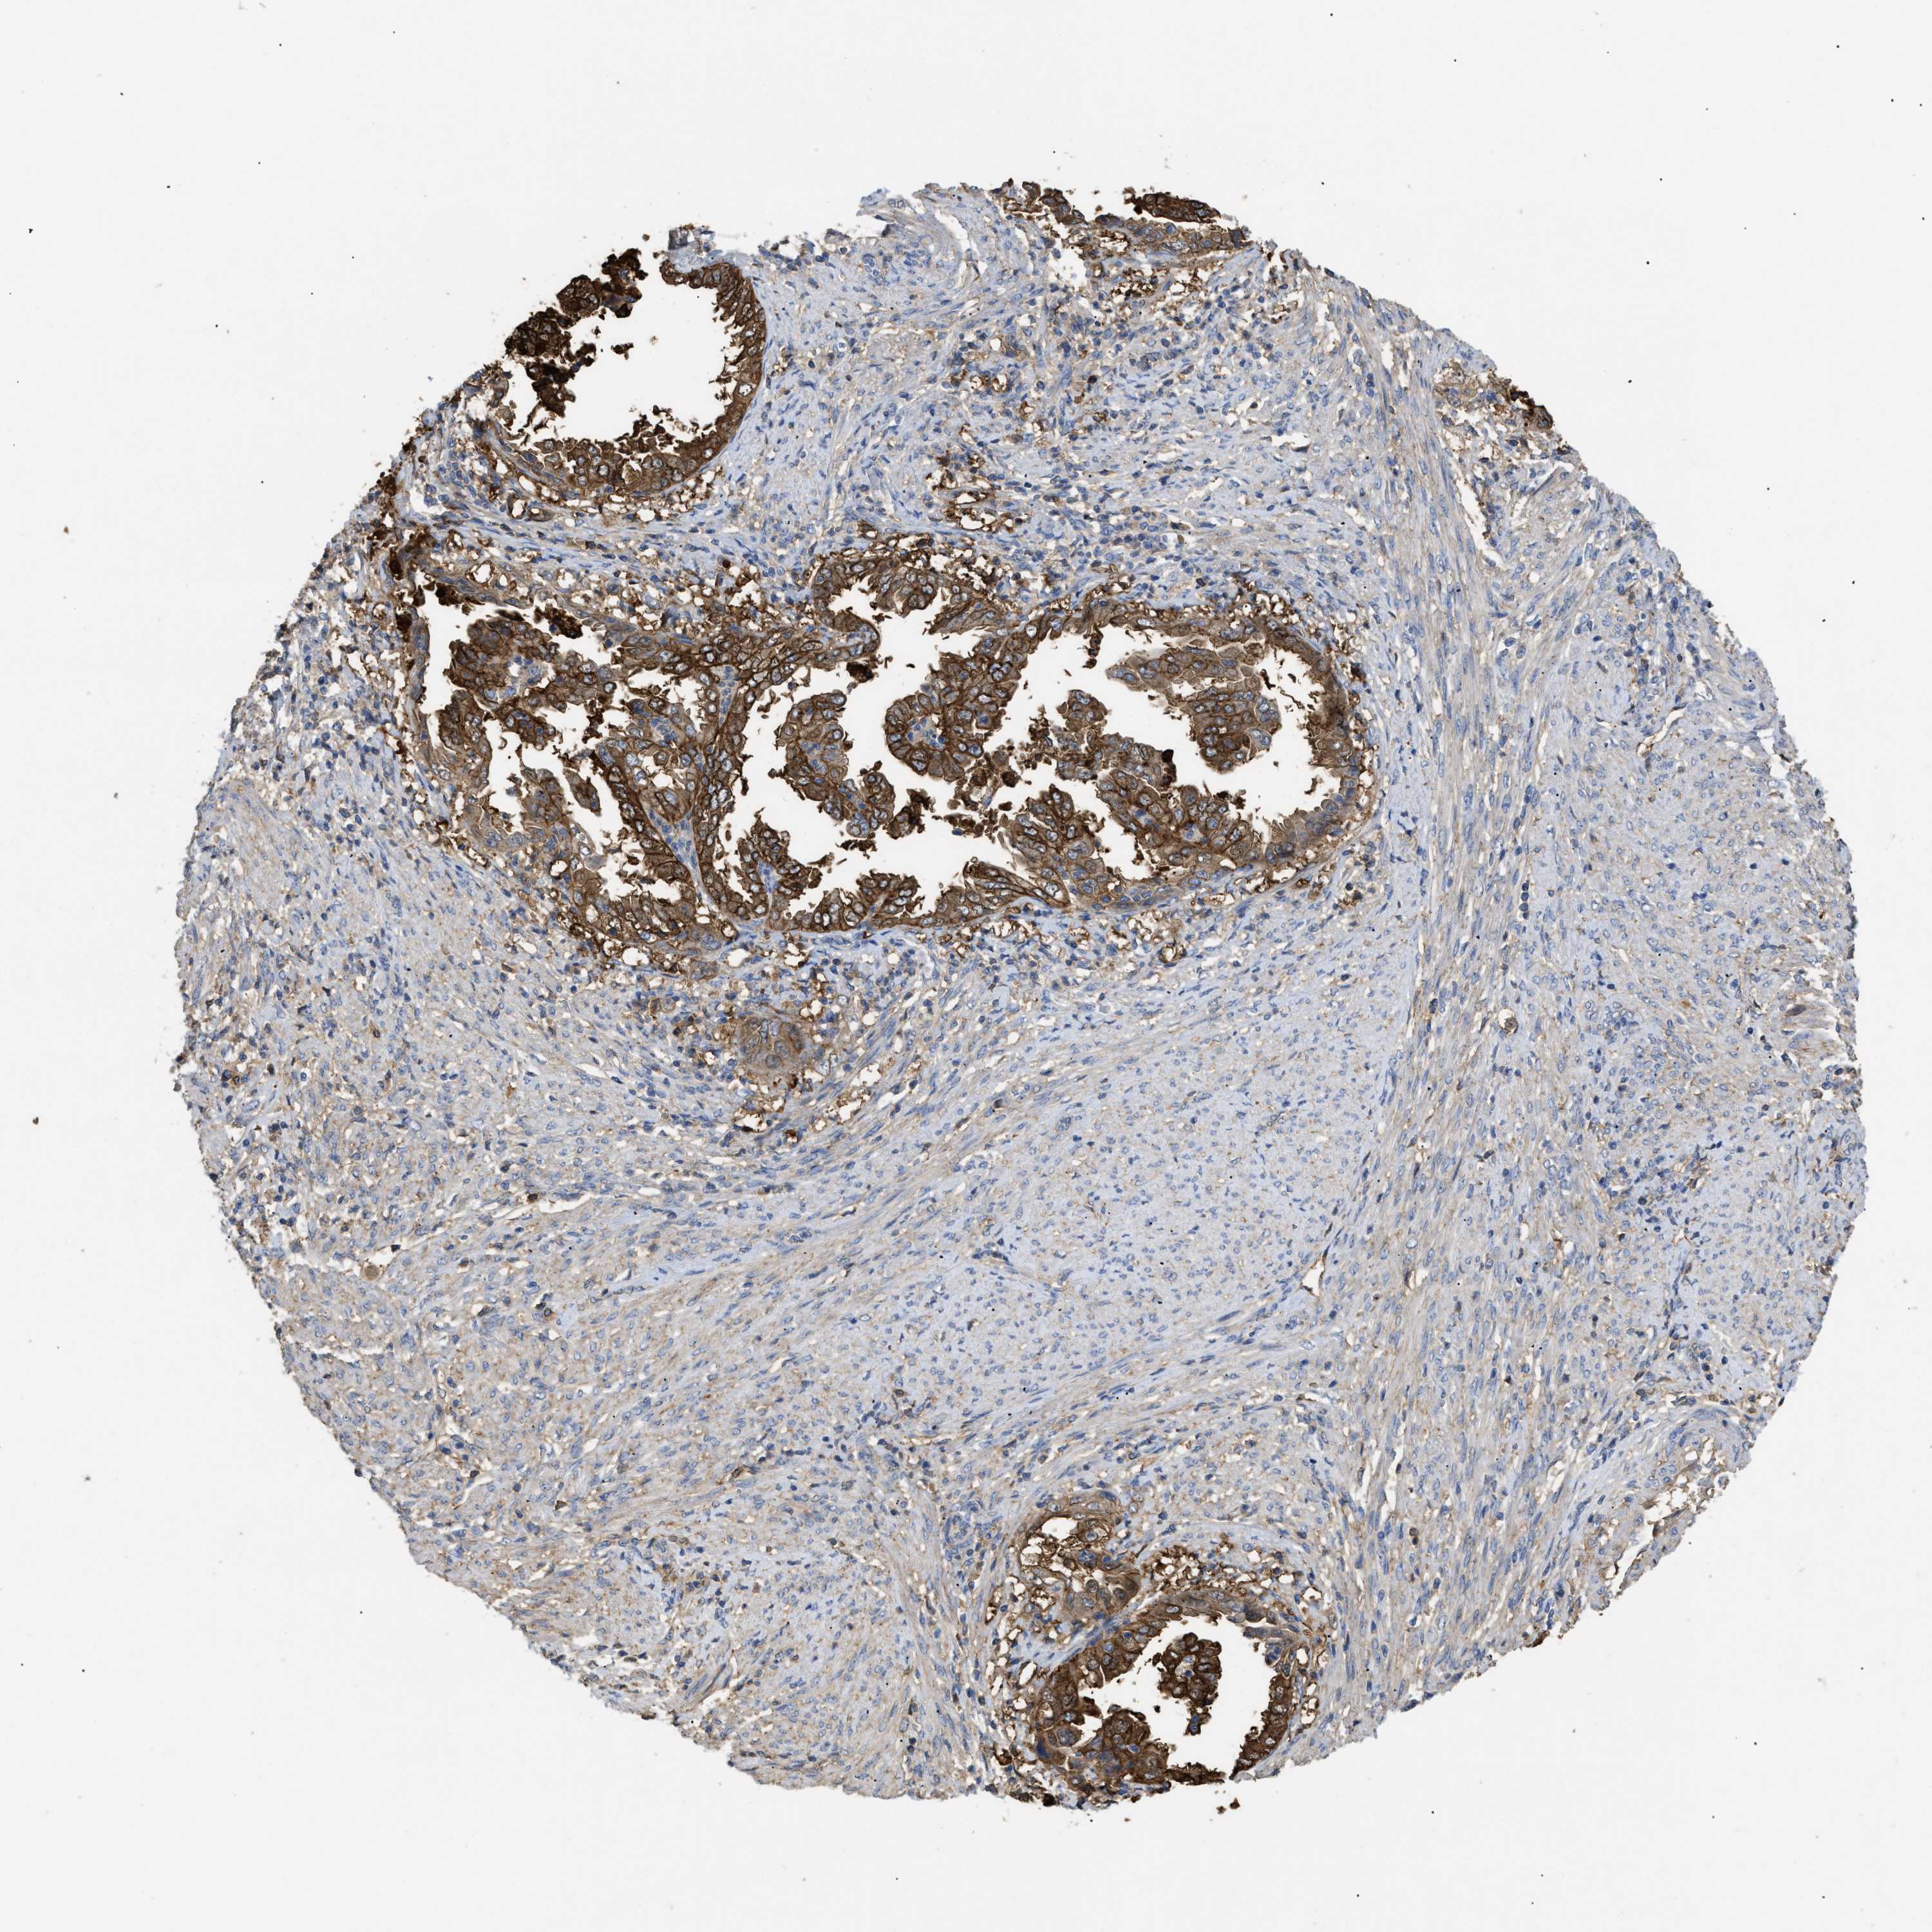

ENDOMETRIAL CANCER - Protein expressioni

A mouse-over function shows sample information and annotation data. Click on an image to view it in a full screen mode. Samples can be filtered based on level of antibody staining by selecting one or several of the following categories: high, medium, low and not detected. The assay and annotation is described here.

Note that samples used for immunohistochemistry by the Human Protein Atlas do not correspond to samples in the TCGA dataset.

Antibody stainingi

Antibody staining in the annotated cell types in the current human tissue is reported as not detected, low, medium, or high, based on conventional immunohistochemistry profiling in selected tissues. This score is based on the combination of the staining intensity and fraction of stained cells.

Each image is clickable and will lead to virtual microscopy that enables deeper exploration of all samples and also displays staining intensity scores, fraction scores and subcellular localization as well as patient and tissue information for each sample.

Antibody HPA007393

Antibody CAB005076

Antibody CAB017560

Location

Nuclear

Cytoplasmic/membranous

Cytoplasmic/membranous,nuclear

Adenocarcinoma, NOS

Neoplasm, malignant, NOS